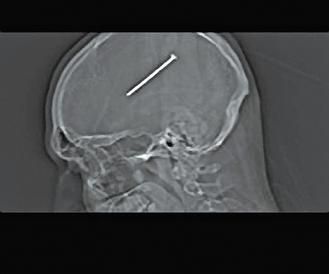

这张X光片中可以清楚看见打进芝加哥男子奥图洛脑子里的长钉。

经X光检查,发现他头上有根钉子,而且只差一点点就伤到控制运动机能的部分。医生立刻动手术,花了四个小时把钉子取出来,并用网子和钛金属板替代他的部分头壳。医生表示,手术很成功,不过仍需在加护病房观察,以免出现并发症。